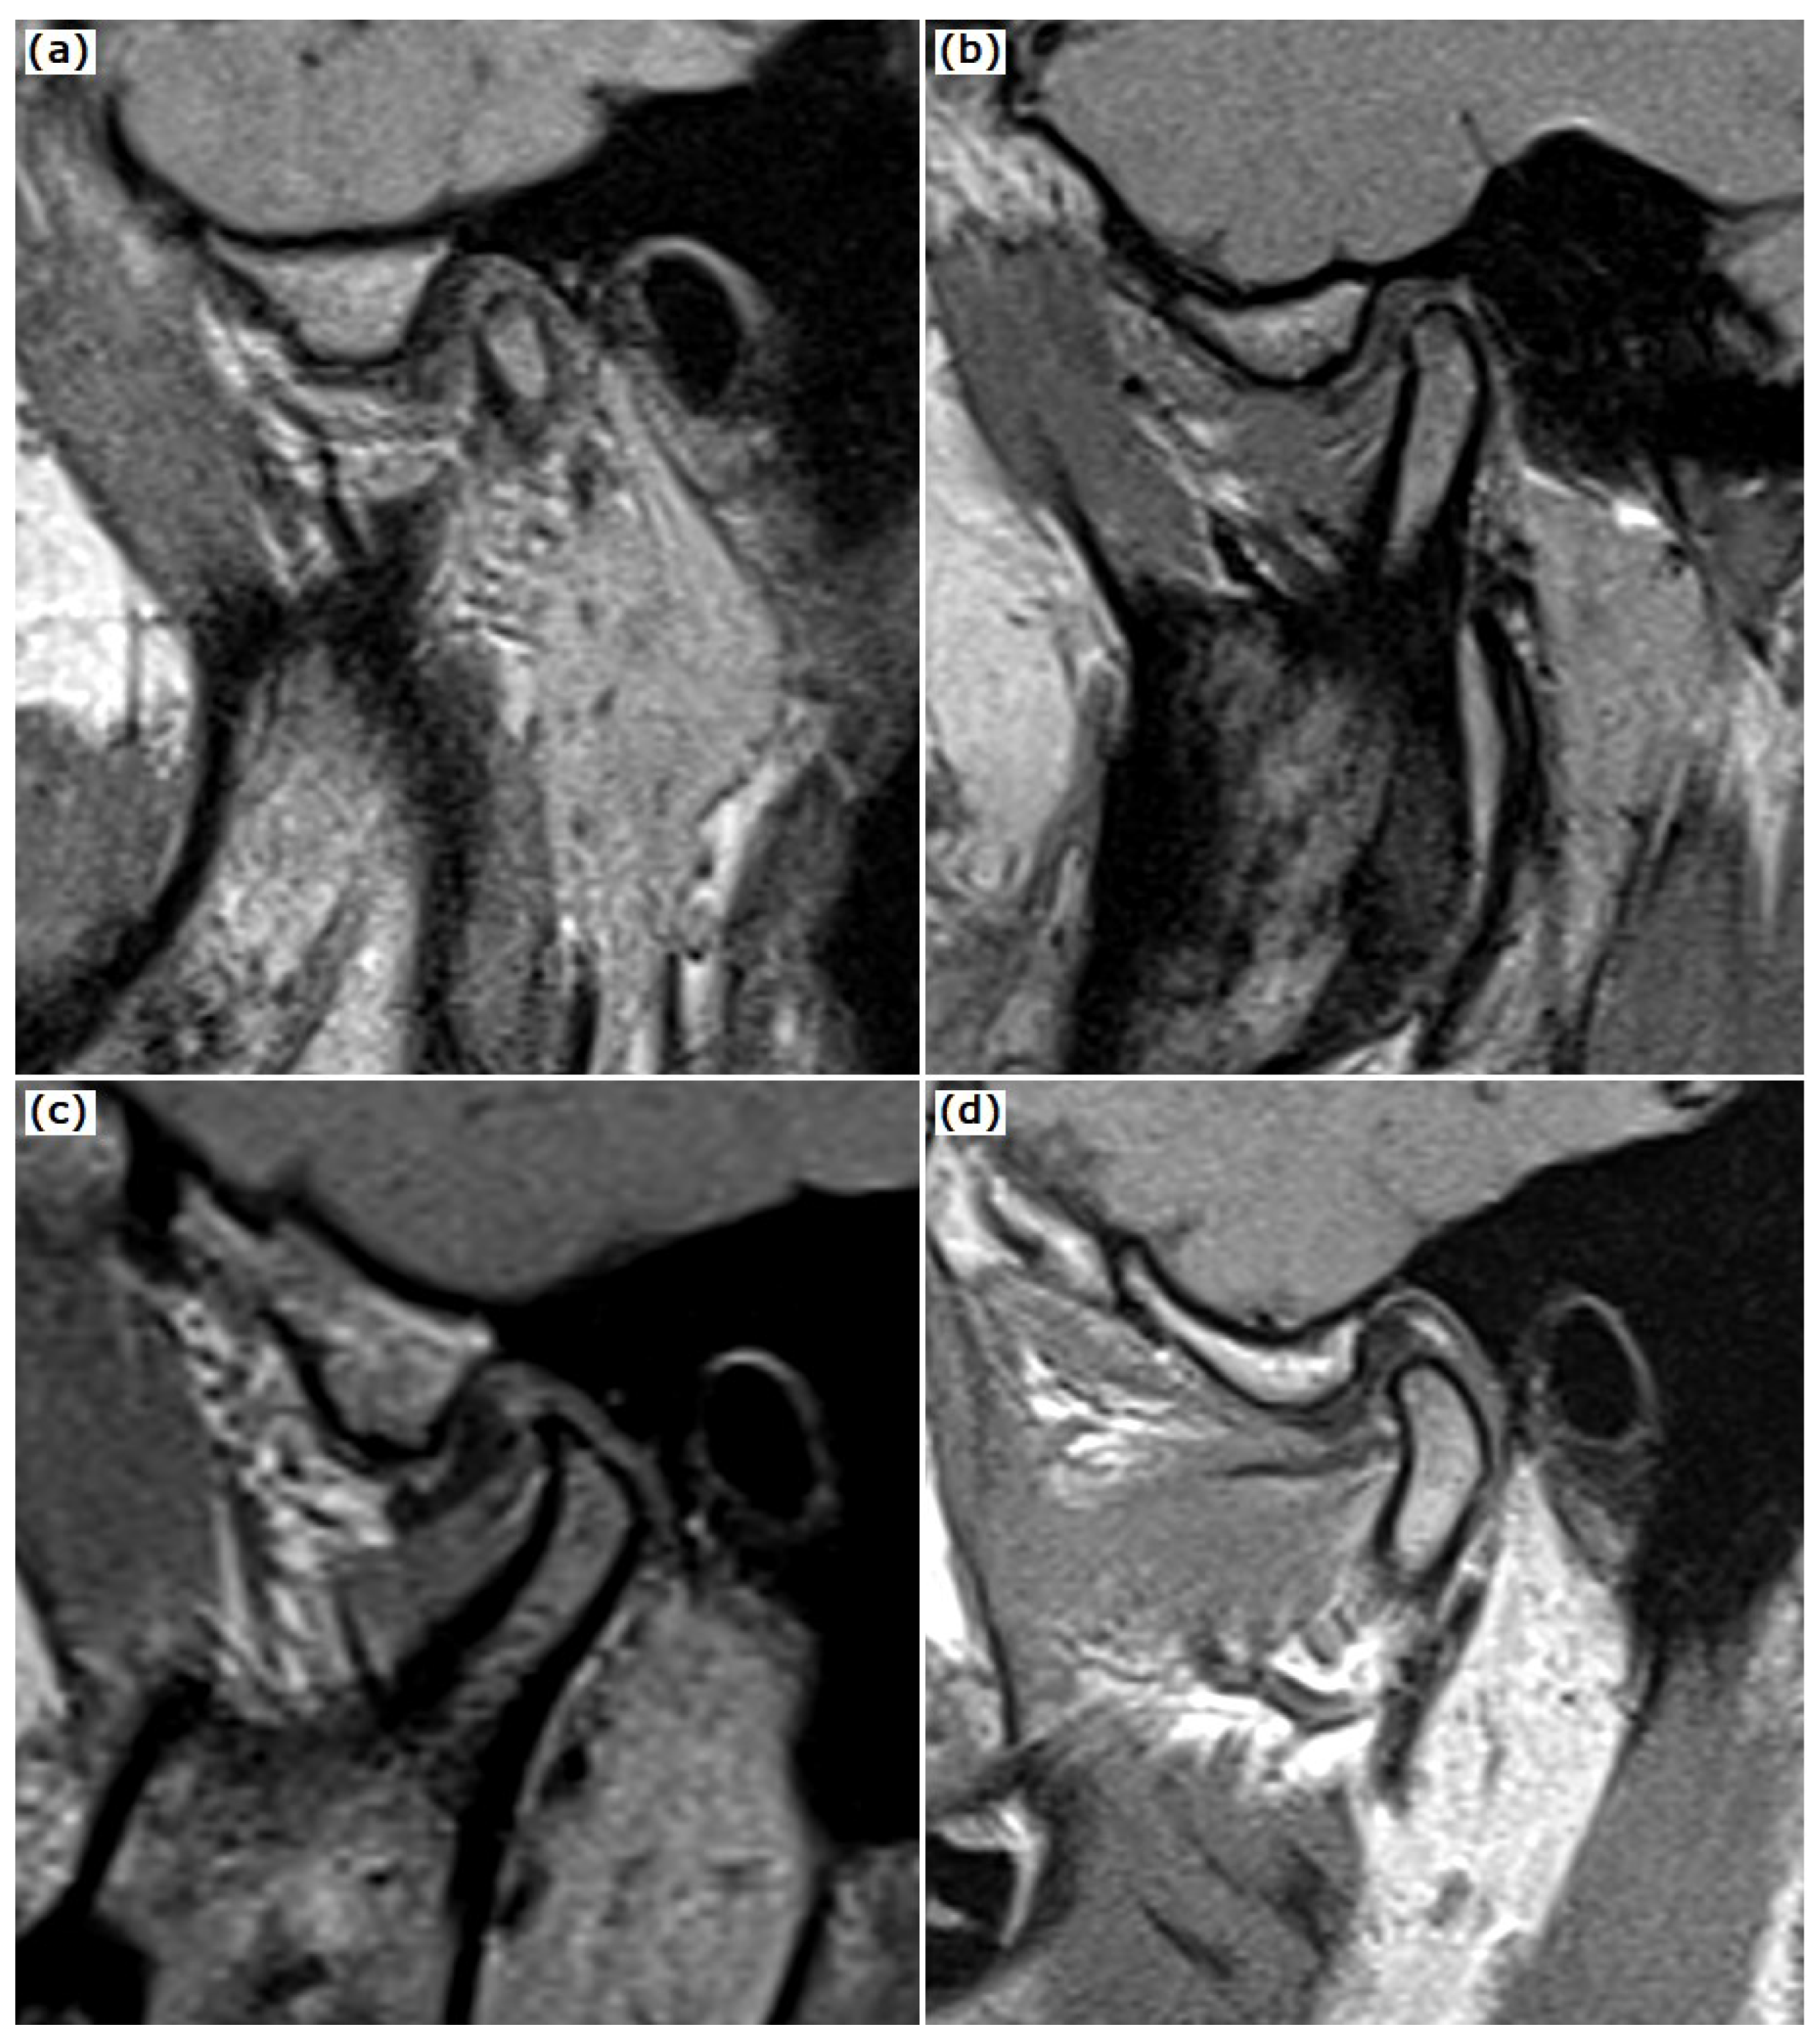

2.1. MRI Examination

2.2. CBCT Examination of the TMJ and the Temporal Bone